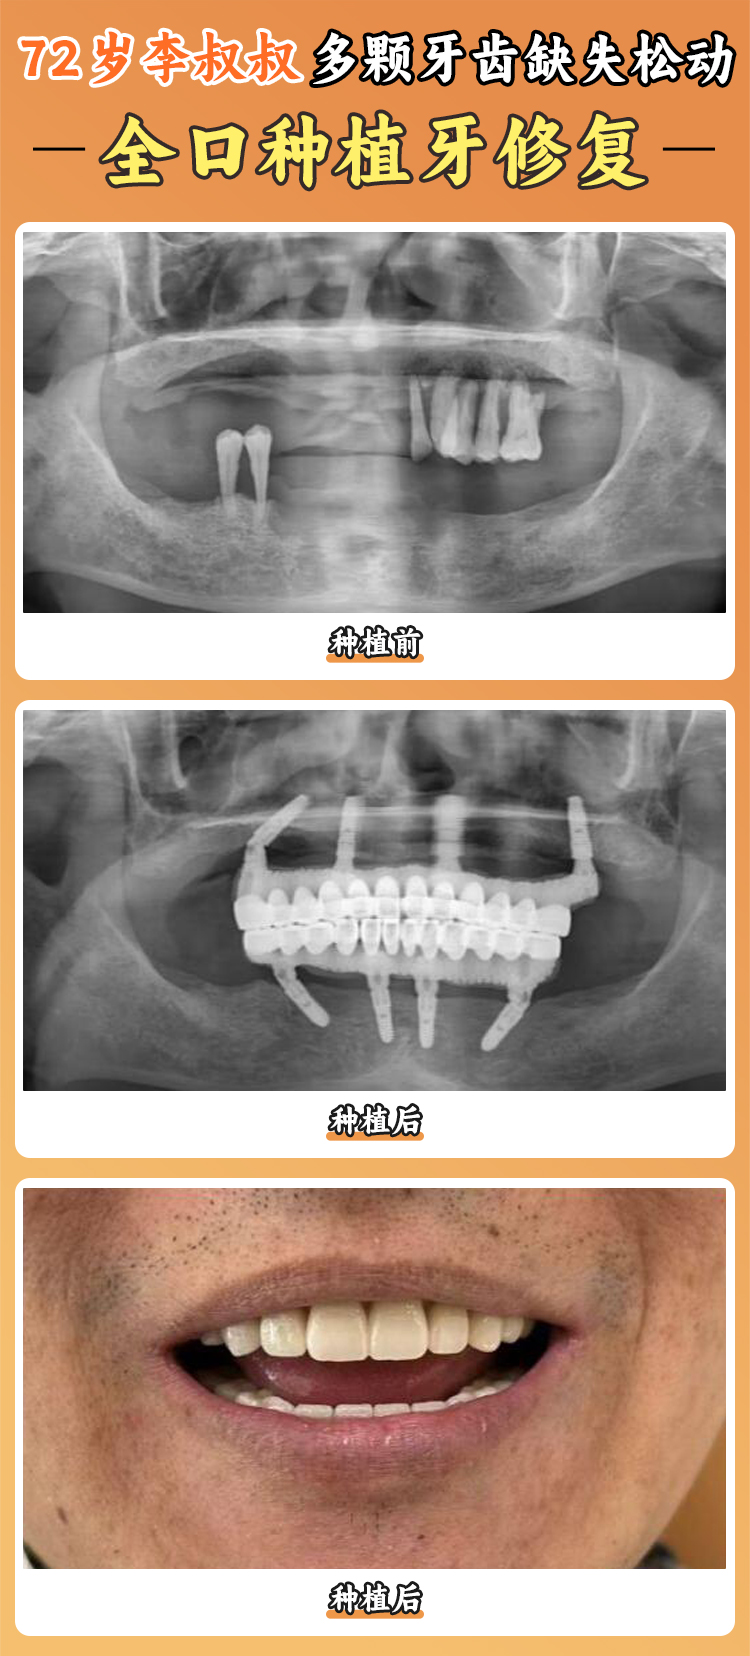

醫(yī)院擁有一支由經(jīng)驗充足的口腔種植醫(yī)師組成的醫(yī)療團隊。這些醫(yī)生就像是經(jīng)驗多的工匠,具備扎實的專科知識和豐富的臨床經(jīng)驗。他們能夠根據(jù)每個患者的不同情況,提供個性化的種植方案,就像為每個人量身定制一件衣服一樣。比如,有的患者牙槽骨條件不太好,醫(yī)生就會采用特殊的種植技術(shù)和方案,確保手術(shù)的可靠性和成效。有一位患者牙齒缺失多年,牙槽骨萎縮重度,其他醫(yī)院都表示治療難度大,但在寧波好牙引領(lǐng)口腔醫(yī)院,醫(yī)生憑借豐富的經(jīng)驗和不錯的技術(shù),成功為他種上了牙齒。